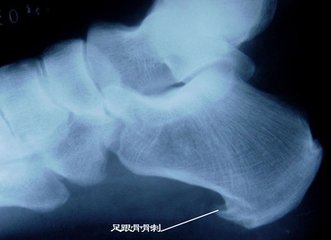

前面我们也介绍过骨刺的发生原因和产生机理。骨刺(骨赘)是人的机体对于应力、磨损、炎症等的一种反应,通过这种适应性反应,可以起到稳定局部环境,维持机体的功能,从这个角度上说,骨刺是一种正常的代偿反应,并非多余。

虽然骨刺是医生诊断骨性关节炎的一个依据,但绝大多数不是引起局部疼痛的真正原因,更不是它直接引起疼痛症状。只有当局部的骨刺对周围的软组织产生顶压等刺激时,才会引起局部的疼痛症状,并且这种情况非常少见。